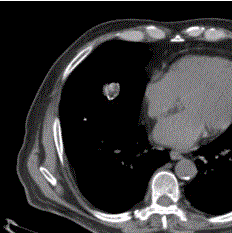

问题 患者男,体检时发现肺内结节,行CT检查如下图。应诊为

选项 A.结核球 B.周围型肺癌 C.炎性假瘤 D.错构瘤 E.钙化灶

答案 D